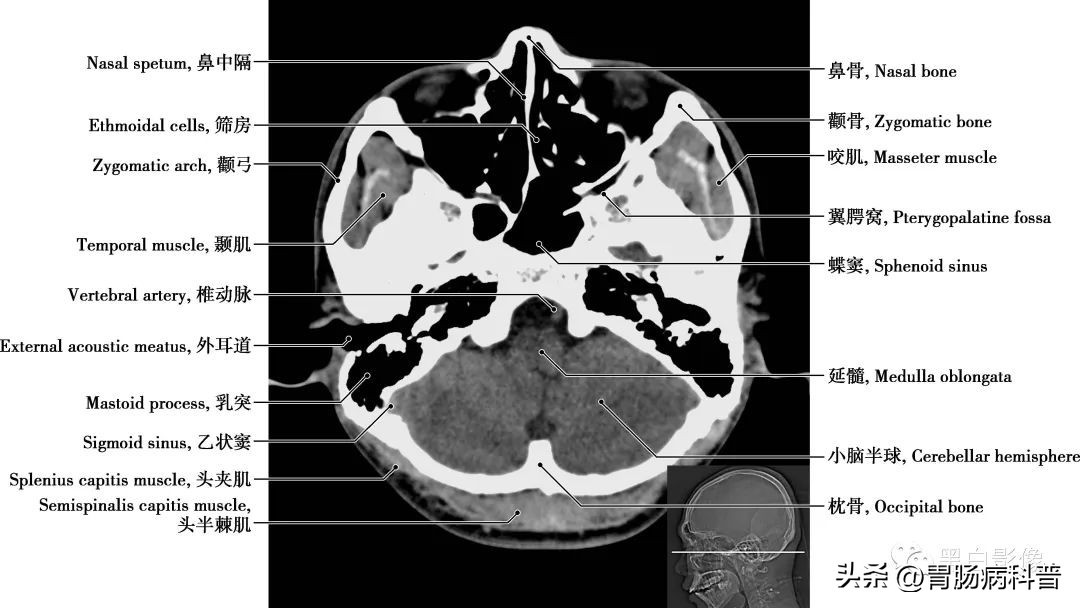

图1-1-18 经下颌头轴位切面

枕大池 又称小脑延髓池,位于颅后窝的后下部,小脑下面、延髓背侧面与枕鳞下部三者之间。向前经小脑溪通第四脑室;向前外经延髓侧面通延髓池。咽鼓管 咽鼓管从鼓室口向内、向前、向下直到咽口,是沟通鼓室与鼻咽部的通道,软骨部平时闭合,仅在吞咽或呵欠时开放,以平衡中耳和外耳的气压,有利于鼓膜的正常振动

图1-1-19 经小脑扁桃体轴位切面

上颌窦 为上颌骨体内的锥形空腔,位于上颌骨体内,窦壁为骨质,覆黏膜,向内侧开口于中鼻道,分为一底、一尖及前、后、上、下四个壁。由于窦口高于窦底部,故在直立位时若有炎性物不易自然流出。外耳道 为外耳门至鼓膜的管道,呈弯曲状,由外向内,先向前上,继而稍向后,弯向前下